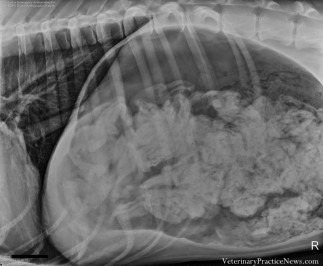

X-rays turned up what Dr. Ashley Magee described as “a lot of foreign material,” when worried owners brought the sick animal to Dove Lewis for emergency surgery in February.

Opening up the dog’s stomach, the material turned out to be sock after sock after sock – 43 1/2 socks in all.

The story has just now come to light, because Dove Lewis entered the great Dane’s x-ray in an industry journal competition for Veterinary Practice News.